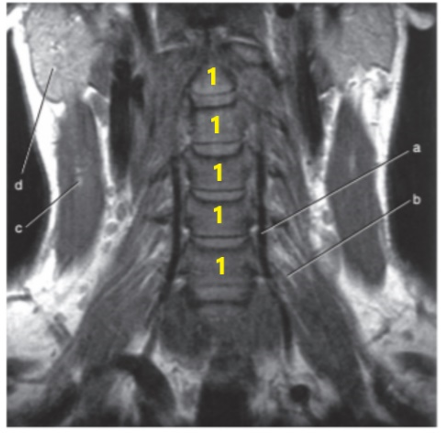

What is # 1's ?

Cervical spine